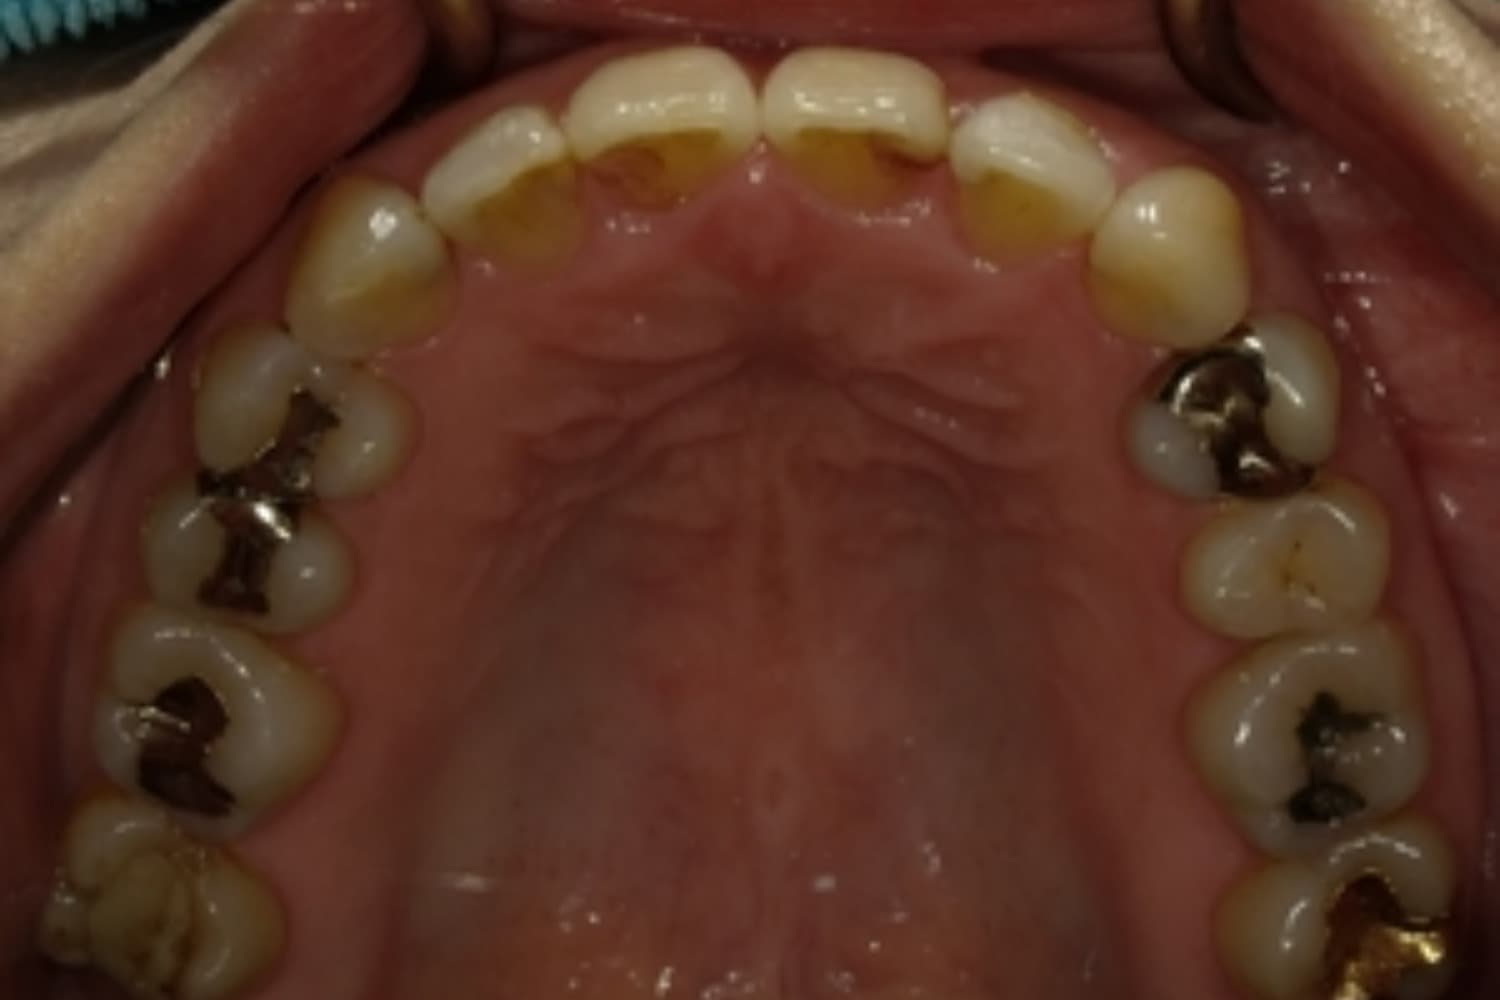

すきっぱ(空隙歯列)2

Before

After

気になる前歯の隙間と前歯のガタガタをマウスピース矯正(インビザライン)にて治療

治療期間

1年

費用

88万円(税込)